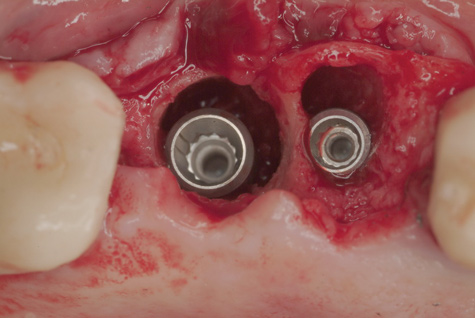

(4.) The implant in the molar position was relatively narrow and failed biomechanically. It was removed with a trephine, and the adjacent fractured bicuspid was also extracted to accommodate an implant. Because sufficient apical bone was present, a wider implant was placed in the molar position. Bone augmentation was performed around both implants.

Figure 4

(5.) The implant in the molar position was relatively narrow and failed biomechanically. It was removed with a trephine, and the adjacent fractured bicuspid was also extracted to accommodate an implant. Because sufficient apical bone was present, a wider implant was placed in the molar position. Bone augmentation was performed around both implants.

Figure 5